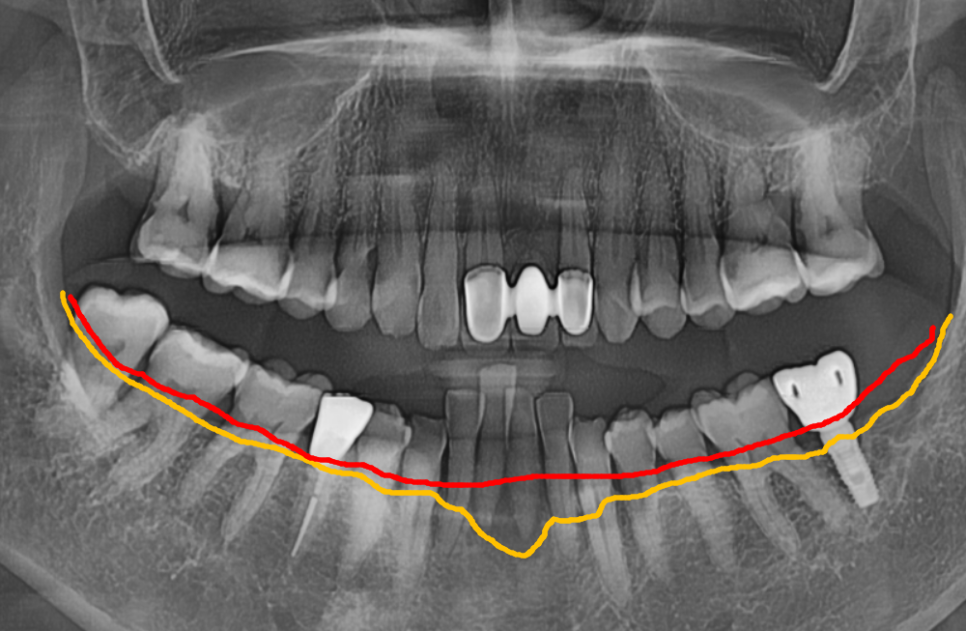

뼈이식은 필수가 아닙니다.

꼭 필요한 경우에만 진행합니다.

솟구치는 앞니, 흔들리는 치아가 보내는 '이 신호' 무시하면 안 되는 이유

뼈이식은

모든 임플란트에 필수가 아닙니다.

뼈이식을 하게 되면 비용 부담은 물론이고,

수술 기간도 3~6개월 이상 길어집니다.

회복 과정에서 불편함도 있고요.

그래서 저희는 CT로 뼈의 폭과 높이를

정밀하게 분석한 뒤,

뼈이식이 필요하지 않은 경우

불필요한 시술을 권하지 않습니다.

이번 환자분의 경우,

CT 분석 결과 남아 있는

뼈의 양과 밀도가

임플란트를 식립하기에 충분했습니다.

그래서 뼈이식 없이

발치 당일 즉시 임플란트를 식립하는

방식으로 진행했습니다.